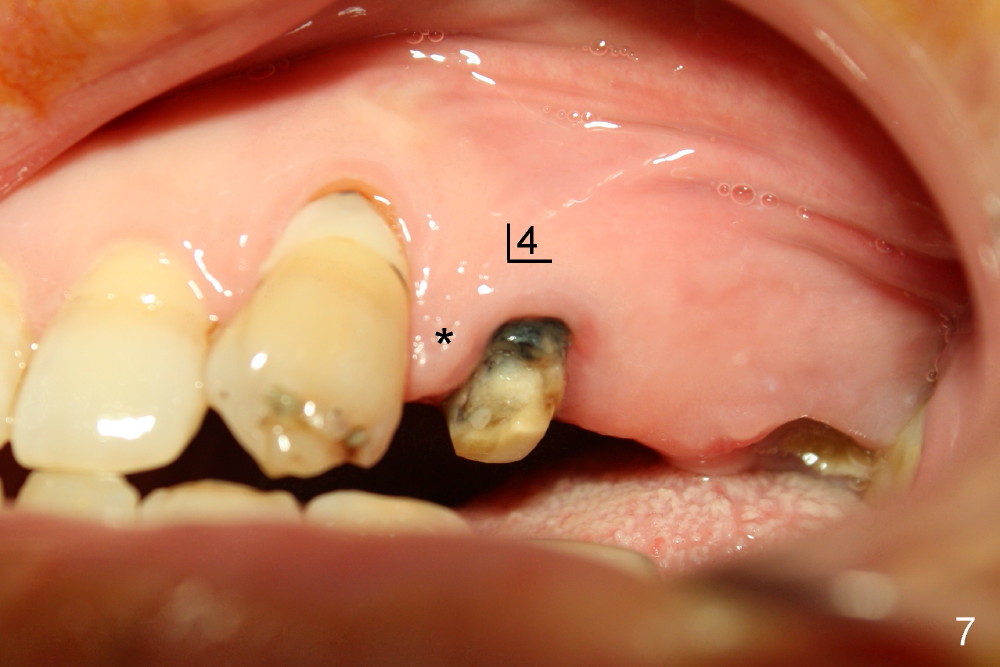

A 47-year-old lady has lost an upper left bridge (Fig.4,7). She is a dental phobic, but is concerned about cosmetics. Immediate implant and immediate provisional for the 1st bicuspid are easily accepted. There is a sinus septum above. Intraop PAs show that 4.5x17 mm tap (Fig.5) and 5x17 mm implant (Fig.6, insertion torque > 60 Ncm) are placed mesial to the septum without sinus membrane perforation. An abutment is placed immediately and an immediate provisional is fabricated.